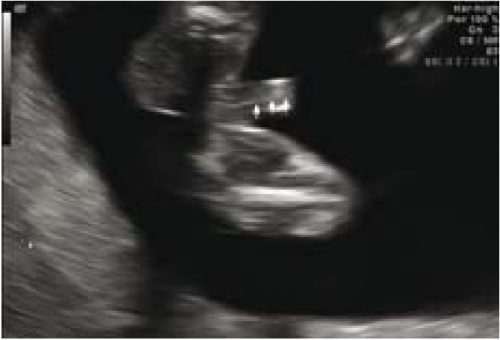

ברונשטיין וחב׳[7] דיווחו שדיוק אבחון מין העובר על ידי אולטרסאונד נרתיקי עולה עם הניסיון, כך שבשנתיים הראשונות לשימוש באולטרסאונד נרתיקי, המין אובחן בדיוק של 76 אחוז ועלה ל-80 אחוז בשנתיים לאחר מכן בין השבועות 14-13 להיריון, ובשבוע 16-15 הדיוק עלה מ-88 אחוז בשנתיים הראשונות לנסיונם ל-96.7 אחוז בשנתיים לאחר מכן. בעבודה זו, מין זכר נקבע על סמך הדגמת מבנה דמוי כיפה (dome sign) המייצג שק אשכים (תמונה 3) בעוד מין נקבה נקבע על סמך הדגמת שניים או ארבעה קווים מקבילים (parallel lines) המייצגים את השפתיים הקטנות והגדולות (תמונה 4) . סימנים סונוגרפיים נוספים בעבודה זו[7] היו הדגמת קו אקוגיני הנמשך מבסיס ועד קצה איבר המין הזכרי ומייצג קו האמצע של הפניס (תמונה 5) וכיוון הפאלוס העוברי (כלפי מעלה מייצג זכר וכלפי מטה נקבה).